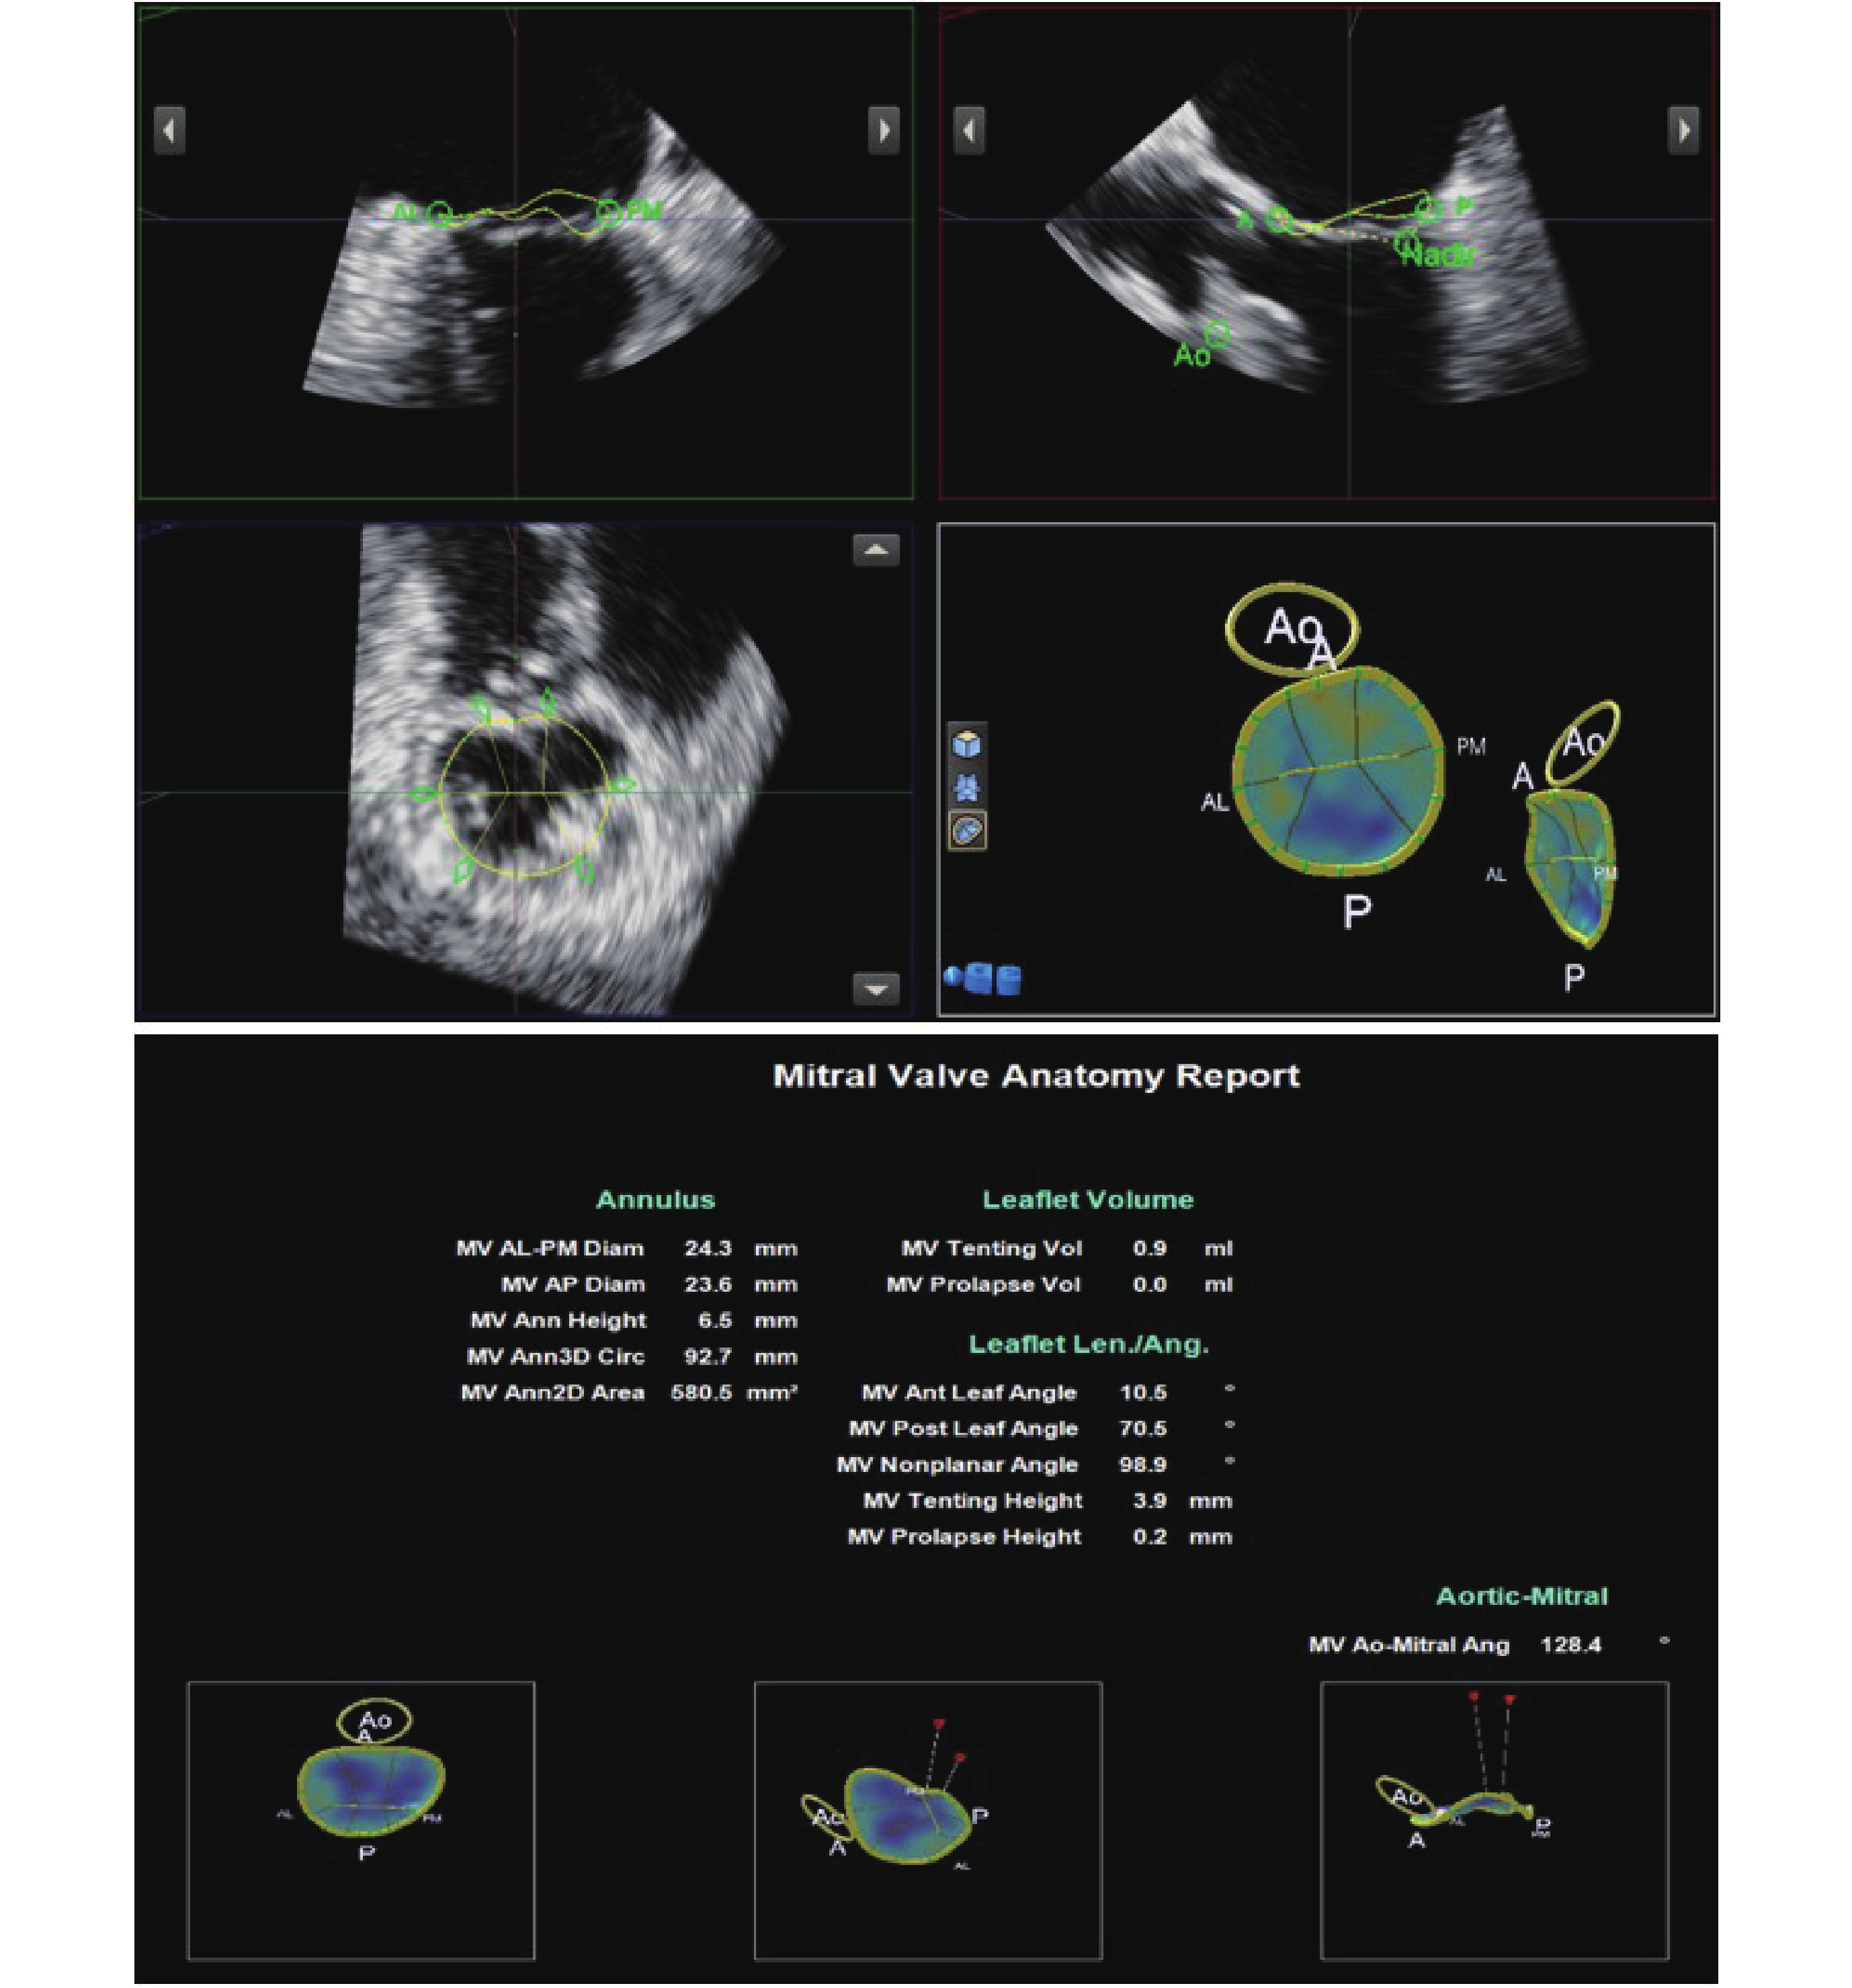

所有患者的三維數據經QLAB軟件對二尖瓣裝置結構進行分析。觀察指標包括:(1)瓣環結構參數4個;(2)瓣葉結構參數7個:其中反映瓣葉重構程度的指標2個、反映瓣葉毀損程度的指標2個、反映瓣葉朝向及栓系力度的指標2個、反映前后瓣葉相互運動模式及瓣體張力分布的指標1個;(3)主動脈瓣-二尖瓣角度(°)。三維數據分析及結果導出見圖1,參數解讀見表1[9-10]。